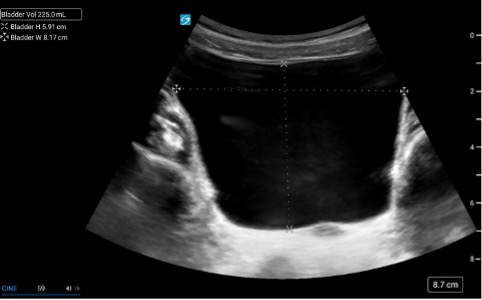

Bladder Volume Technique:

Bladder volume can be determined non-invasively by measuring the bladder in its maximal width, depth, and length. Bladder volume can be calculated both pre- and post-void.

1. Scan the bladder in two planes to obtain three unique measurements (Figure 2)

> Width: In the transverse plane, measure the diameter between the lateral walls to obtain the width.

> Depth (height): is the anteroposterior diameter, which can be obtained in the transverse or sagittal plane. Choose just one plane for this measurement.

Length: is the craniocaudal diameter, which is obtained by measuring from the superior to inferior wall of the bladder in the sagittal plane.

2. Calculate Volume

> Most current machines contain automated calculators for volume measurement.

> As an alternative, the simple formula (LX W X D X 0.7) can be used to estimate bladder volume.

– However, because of the inherent variability of bladder shape and the variation in this shape with differing degrees of filling, bladder volume measurements obtained in this fashion may have an error rate between 15% and 35% [10].

Figure 2: Measurements for bladder volume in transverse and sagittal planes [11]

Figure 3 & 4: Caliper placement for bladder volume in the transverse and sagittal planes.